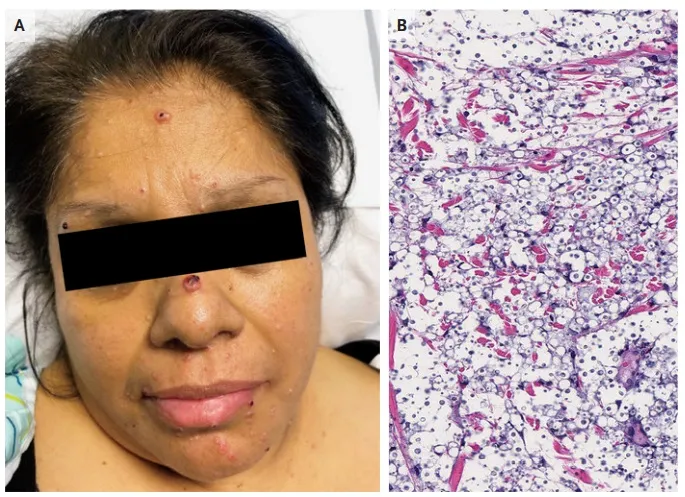

IRA + Icterícia: Um Caso que Exige Investigação Detalhada

IRA + Icterícia: Um Caso que Exige Investigação Detalhada